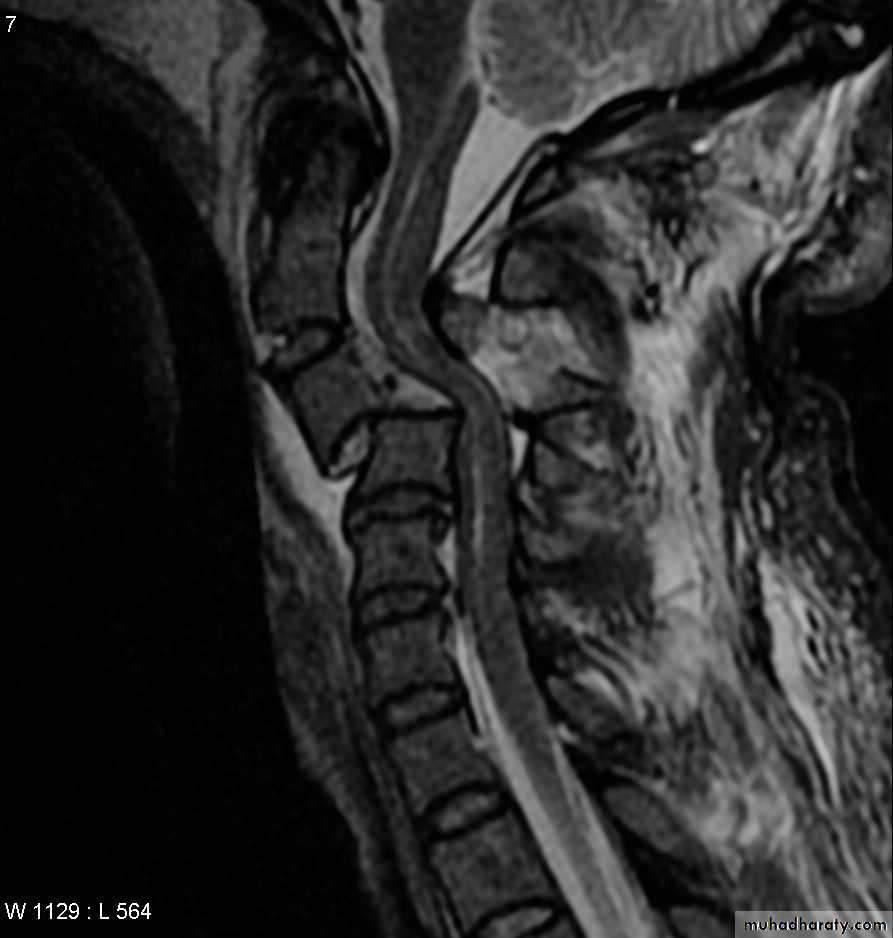

DIAGNOSISX RAY

Anterio posterior X ray radiograph.lateral radiographs with the head in flexion and extension may revealinstability that is not shown in the routine lateral film.

through the open mouth.Computed tomography (CT)

and magnetic resonance imaging (MRI).

A hyperextension

force may fracture the neural arch, especially of the atlas

Or fracture the dens (odontoid process) of the axis.

hyperextension may rupture the anterior longitudinal ligament and the

anulus fibrosus, forcing the vertebral bodies apart anteriorly (extensionsubluxation) .